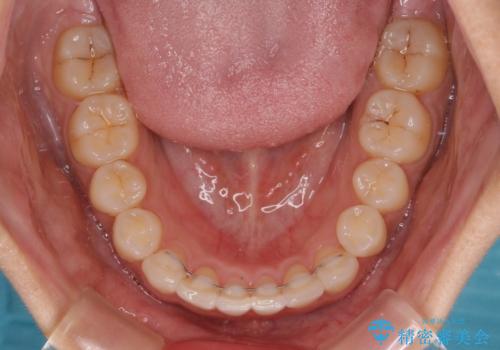

- 上下前歯のデコボコを気にして来院された患者様です。

ワイヤー矯正でもインビザラインでも、どの装置でも対応可能でしたが、安価で楽して素早く治療を終えたいとのことで、メタルブラケット装置による矯正治療を行うこととしました。